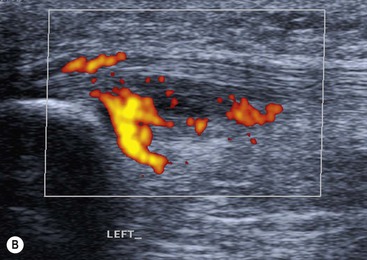

The affected tendon is thickened and hyporeflective on US, with neovascularisation on Doppler imaging (Fig. 46-16). High SI is demonstrated on fluid-sensitive MRI sequences (Fig. 46-17). Tendon tears are demonstrated as focal areas of deficiency.13 In chronic cases, new bone formation may be seen on radiographs at the tendon enthesis. Calcific tendinopathy is much less common than in the rotator cuff of the shoulder.